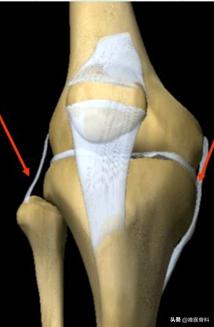

一、膝关节内、外侧副韧带的介绍

在我们的膝关节两侧,有两条主要的韧带平行存在,即膝关节内、外侧副韧带。这两条副韧带紧紧连接着膝关节远、近两端,对维持膝关节的稳定性起着十分重要的作用。

1、膝关节内侧副韧带

起于股骨内髁结节,止于胫骨内髁侧面,呈现出上宽下窄的扇形,在膝关节内侧与关节囊和内侧半月板相连,其主要作用是防止膝关节伸直位时过度外翻。

2、膝关节外侧副韧带

起于股骨外髁结节,止于腓骨小头,呈条索状,在膝关节外侧不与半月板相连,其主要作用是防止膝关节伸直位时过度内翻。